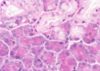

Which stain has been used in the image above to demonstrate the microvillous brush boarder?

- Alcian blue

- H+E

- Iron haematoxylin

- PAS

- Perls

- PAS. These are intestinal villi stained by the PAS procedure (magenta pink stain) and with haematoxylin (blue stain). The wine-glass shaped goblet cells stain dark pink as does the brush border. The nuclei of the columnar epithelial cells stain blue.